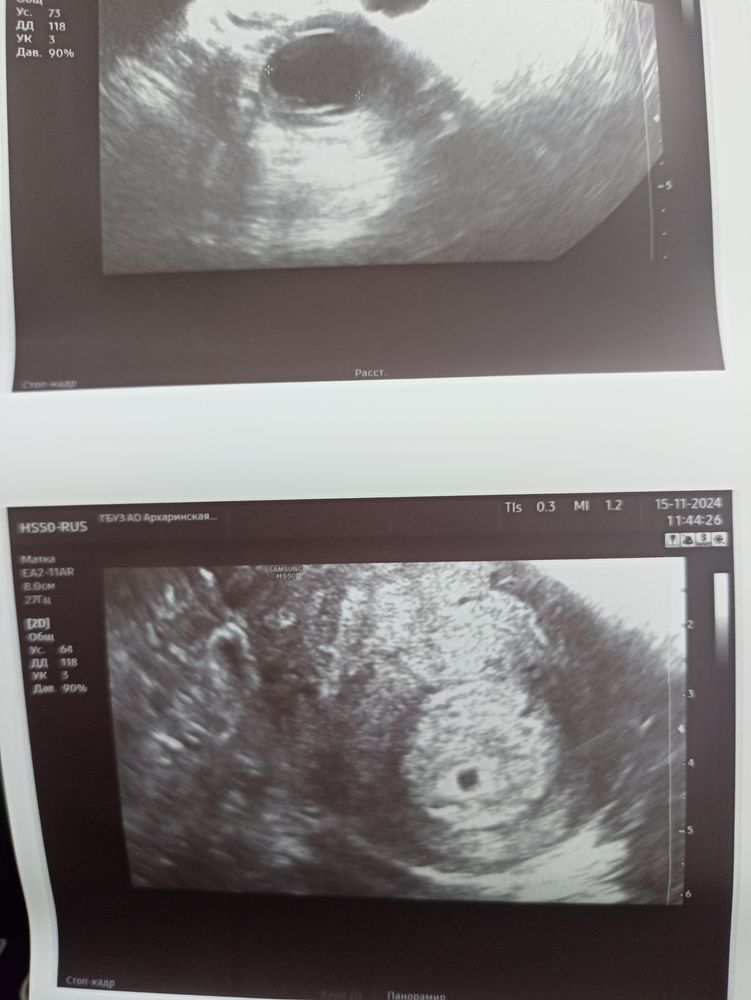

Алёна Хаустова, господи, спасибо вам, дай бог чтобы буся удержался🙏я ведь его уже полюбила, фото увидела, ревела от счастья на эту точечку❤